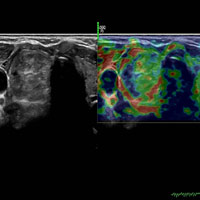

ELASTOGRAPHY

Elastography is an imaging modality that maps the elastic properties of soft tissues such as liver, breast and thyroid. The main purpose is to differentiate between hard and soft tissue thus determining the status of benign and malignant diseases.